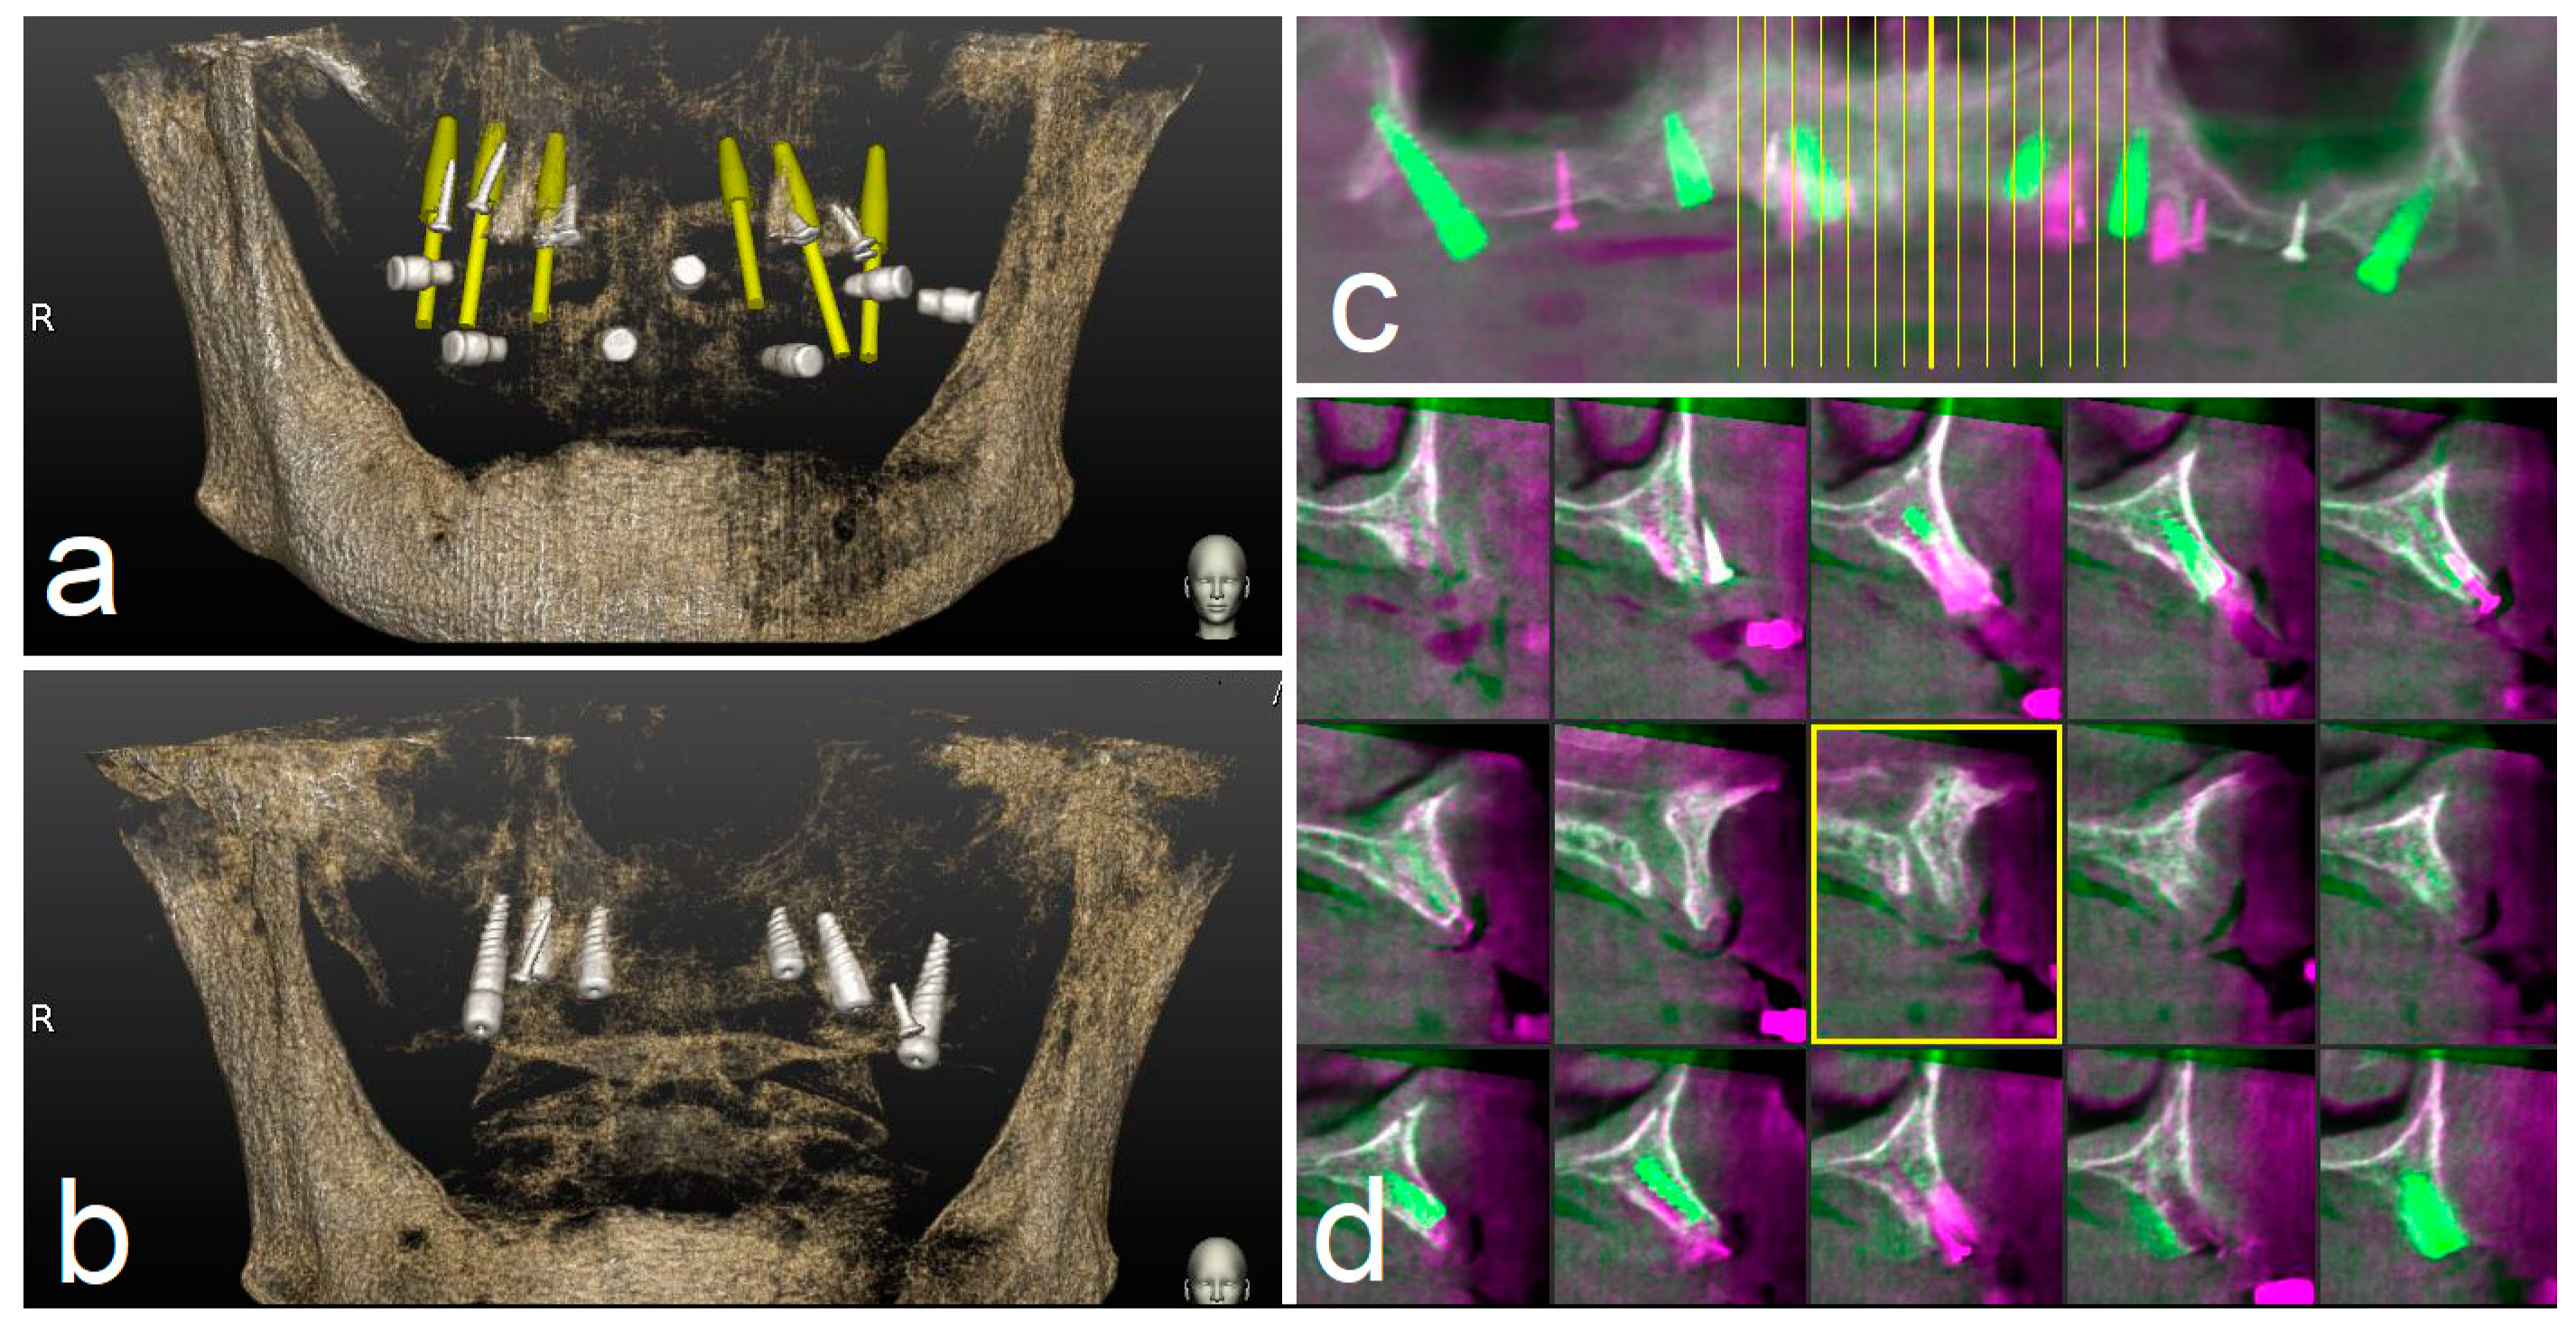

A CBCT (Scanora 3Dx) and an intraoral surface scan (IOS) were taken on each patient. An ideal virtual wax-up of teeth was completed by Lab Technician. Both DICOM files from CBCT and stereolithography (STL) files from the IOS were matched in Navident software and semi-automatically superimposed to residual teeth (or in toothless cases, using reference points in the wax-up) using the provided mesh-to-image registration tool. In addition, the STL files of the final teeth set-up were matched above previous IOS files of the baseline oral conditions and displayed in Navident software to perform prosthetically driven implant planning (Figure 1).

Figure 1.

Implant planning using stereolithography (STL) files as reference for a prosthetic driven implantation (a). Panoramic (b), axial (c), bucco-lingual (d), and parasagittal (e) view.